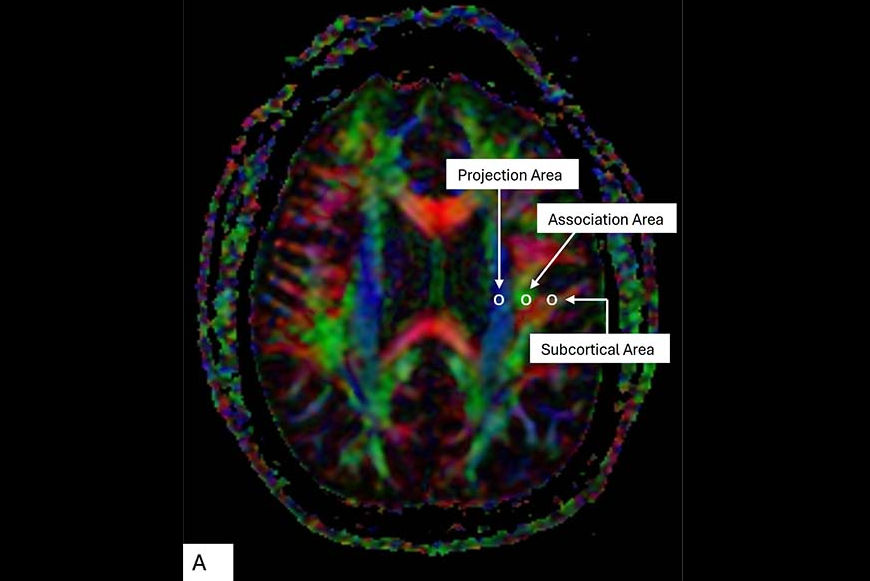

All of the study participants underwent 3-tesla MR imaging. The investigators identified any cerebral microbleeds or other symptoms of cerebral small vessel disease (such as white matter hyperintensities, lacunes, or perivascular spaces) and assessed brain health by tracking individuals' cognition, sleep, depression, gait, and cardiovascular disease risk using the following tools: the Computerized Assessment of Information Processing (COGNITO), the Pittsburgh Sleep Quality Index, the Center for Epidemiologic Studies Depression Scale, clinical interviews, and the Framingham Risk Score (this last is based on age, systolic blood pressure, use of antihypertensive medication, current smoking, diabetes, and cholesterol).